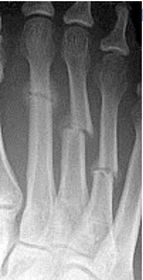

| Describe the alignment of metatarsal 2 | There is no angulation nor displacement of the distal segment relative to the proximal segment. |

| Describe the alignment of metatarsal 3 | The distal segment is displaced laterally (50% apposition) and angulated medially. |

| Describe the alignment of metatarsal 4 | The distal segment is displaced laterally (75% apposition) but there is no apparent angulation. |

| Describe the tubulation of the metatarsals | Metatarsals are overtubulated - decreased girth. |

| Describe the tubulation of the metatarsals | Metatarsals are undertubulated - increased girth. |